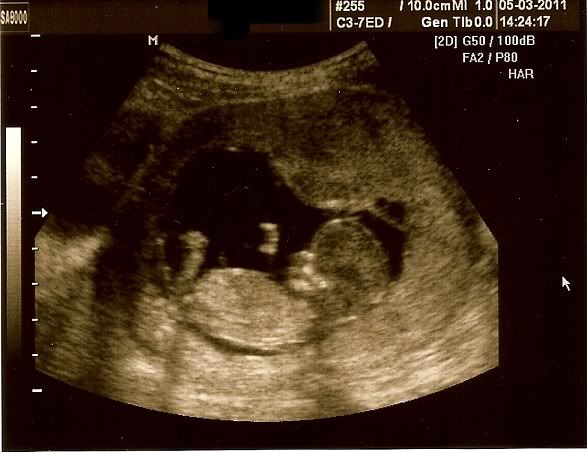

Hier nog even een kiekje van onze beeb, een echo van twee weken geleden (12 weken + 4)